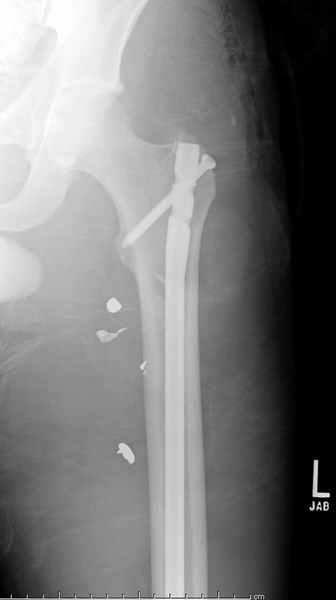

Учитывая, что больной получил травму не во время визита в церковь, и он является одним из представителем 40 миллионного “outstanding itizen”, без медицинской страховки, без работы в свои 39 лет, и без надлежающей ортопедической дисциплины у которого отсутсвует страх стрессового перелома, было рекомендовано оперативное лечение: профилактическое антеградное интрамедуллярное штифтование.

Выглядит агрессивно, и обычно госпиталь, беря финансовые расходы, остается в убытке, но мы всё же посчитали, что издержки от штифтования намного меньше, чем возможные финансовые и моральные издержки лечения таких больных, но с осложнением.

Методика штифтования при отсутствии большой зоны перелома как при онкологических профилактических штифтованиях, расверливание интрамедуллярного канала проводим с предварительным наложением дополнительного дренажного отверстия в дистальном отделе бедра (в данном случаи в канале оставили 6.5 мм канюлированный шуруп), иначе при создании давления в канале во время сверления имеется опасность эмболизации легочной артерии тромбом.